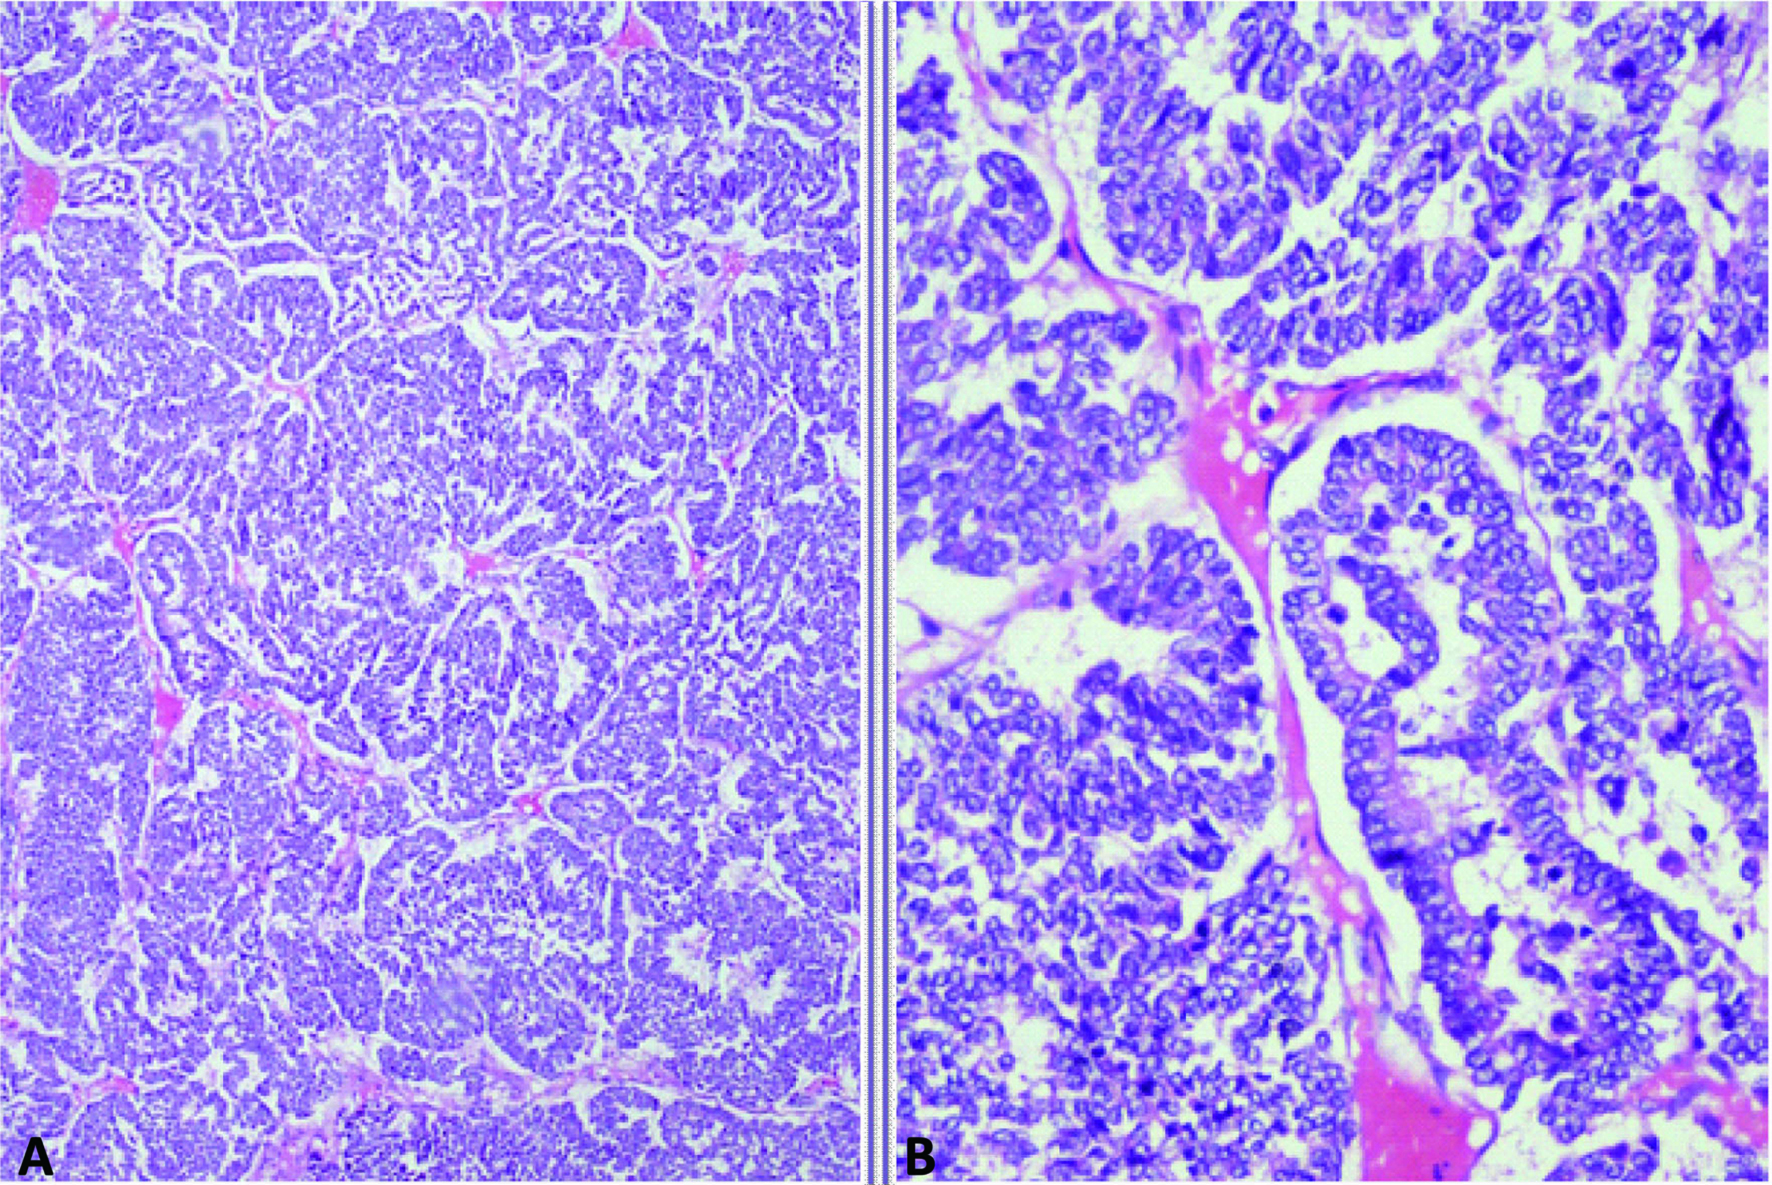

A 40 years old female patient presented with pain upper abdomen, mild to moderate in intensity for 40 days and lump upper abdomen for 10 days. She had history of loss of weight and appetite, but there was no history of cough, fever, jaundice or oral contraceptive intake. On examination, patient was thin built, afebrile, non icteric and hemodynamically stable. Chest and cardiovascular examination were within normal limits. Hepatomegaly was present with an 8 cm x 7 cm lump in the epigastric region. There was no ascites and rectal examination was within normal limit. On laboratory examination, the hemoglobin was 9.8 gm%, serum bilirubin was 0.24 gm%, AST and ALT were 63/53 IU, alkaline phosphate was 572 IU, albumin was 3.5 gm%, PTI was 100%, Alpha Feto Protein was 2.11 ng/dl and CEA level was 1.0ng/ml, which were all within the normal limits. Contrast enhanced computed tomography (CECT) abdomen revealed 13.2 x 13.5 x 7.3 cm well defined mass lesion involving segment IV, V and VIII of liver (Fig. 1). There was rim enhancement on arterial phase and no contrast retention on venous phase. Lesion was compressing the right and left branches of portal vein and there was no ascites. Tumor was involving 58.37 cm2 (38.68%) of the total liver volume. Fine needle aspiration cytology (FNAC) showed features of small cell carcinoma the liver. Upper and lower gastrointestinal endoscopy were normal. Chest x-ray, sputum cytology, chest CECT and bronchoscopy were normal. Positron Emission Tomography (PET) scan revealed 14 x 10 cm mass lesion in liver with metabolic active disease at periphery and central necrosis. No other hypermetabolic lesions elsewhere in body were seen. Patient underwent laparotomy and central bisectionectomy for the tumor arising from segment IV, V and VIII of liver. Histology showed tumor arranged in lobules, nests and trabecular pattern (Fig. 2). Cells were mildly pleomorphic with hyperchromatic nucleus, scanty cytoplasm and many mitotic figures. Features were suggestive of primary small cell carcinoma of the liver. Portal lymph nodes showed metastatic disease. On immunohistochemistry, tumor was positive for neuron-specific enolase and synaptophysin but negative for thyroid transcription factor 1, hep-Par 1 and carcinoembryonic antigen (Fig. 3). Patient recovered well in postoperative period, and was discharged on postoperative day 7. Now patient is on follow-up and undergoing combined chemotherapy.

![]() Click for large image | Figure 2. Photomicrograph showing A: Organoid and trabecular pattern of tumor cells separated by thin fibrovascular septa; B: Tumor cells with finely granular nuclear chromatin and scanty cytoplasm (Haematoxylin and eosin, x 100, x 400). |